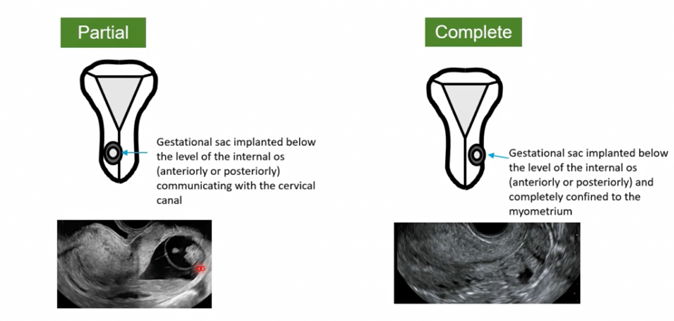

Die uterine ectopic pregnancy und die extrauterine interstitial ectopic pregnancy sollten in partial und complete eingeteilt werden, da dies einen Einfluss auf das Management haben kann.

Partial CSP:

- First-Line Therapie: transzervikale Curettage unter sonographischer Sicht

Complete SCP (sehr selten):

- nicht zugänglich für transzervikale Curettage, Management somit medikamentös mittels MTX i.m. Einmaldosis oder Multi-Dose Schema

Partial intramural uterine ectopic pregnancy:

Complete intramural uterine ectopic pregnancy: